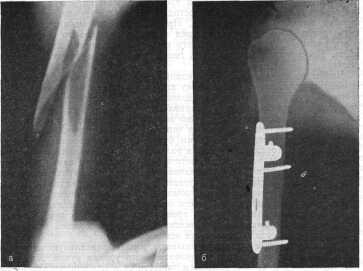

Скрепление пластиной при смещении

По расположению отломков переломы подразделяются на:

- перелом без смещения, характеризующийся травмированием плеча либо надплечья без осколочных сдвигов;

- перелом плечевой кости со смещением, отличающийся обильным либо небольшим сдвигом отломков относительно костной оси и характеризующийся обязательным хирургическим вмешательством. Перелом плеча со смещением требует немедленной медицинской помощи для правильной постановки диагноза.

- со смещением — обломки крепятся специальными стержнями, а через определенное время вынимаются из кости;

- невправляемого обычным путем, при этом применяется пластиночная фиксация без гипса с последующим ее снятием;

- чрезмыщелковых концов, сопровождаемых чаще всего смещением обломков, которые вправляются под анастезией с наложением гипса до 2 месяцев; если не удается устранить смещение – оперативным путем, во время которого применяются винты либо пластины, находящиеся в теле человека несколько лет, что зависит от тяжести травмы;